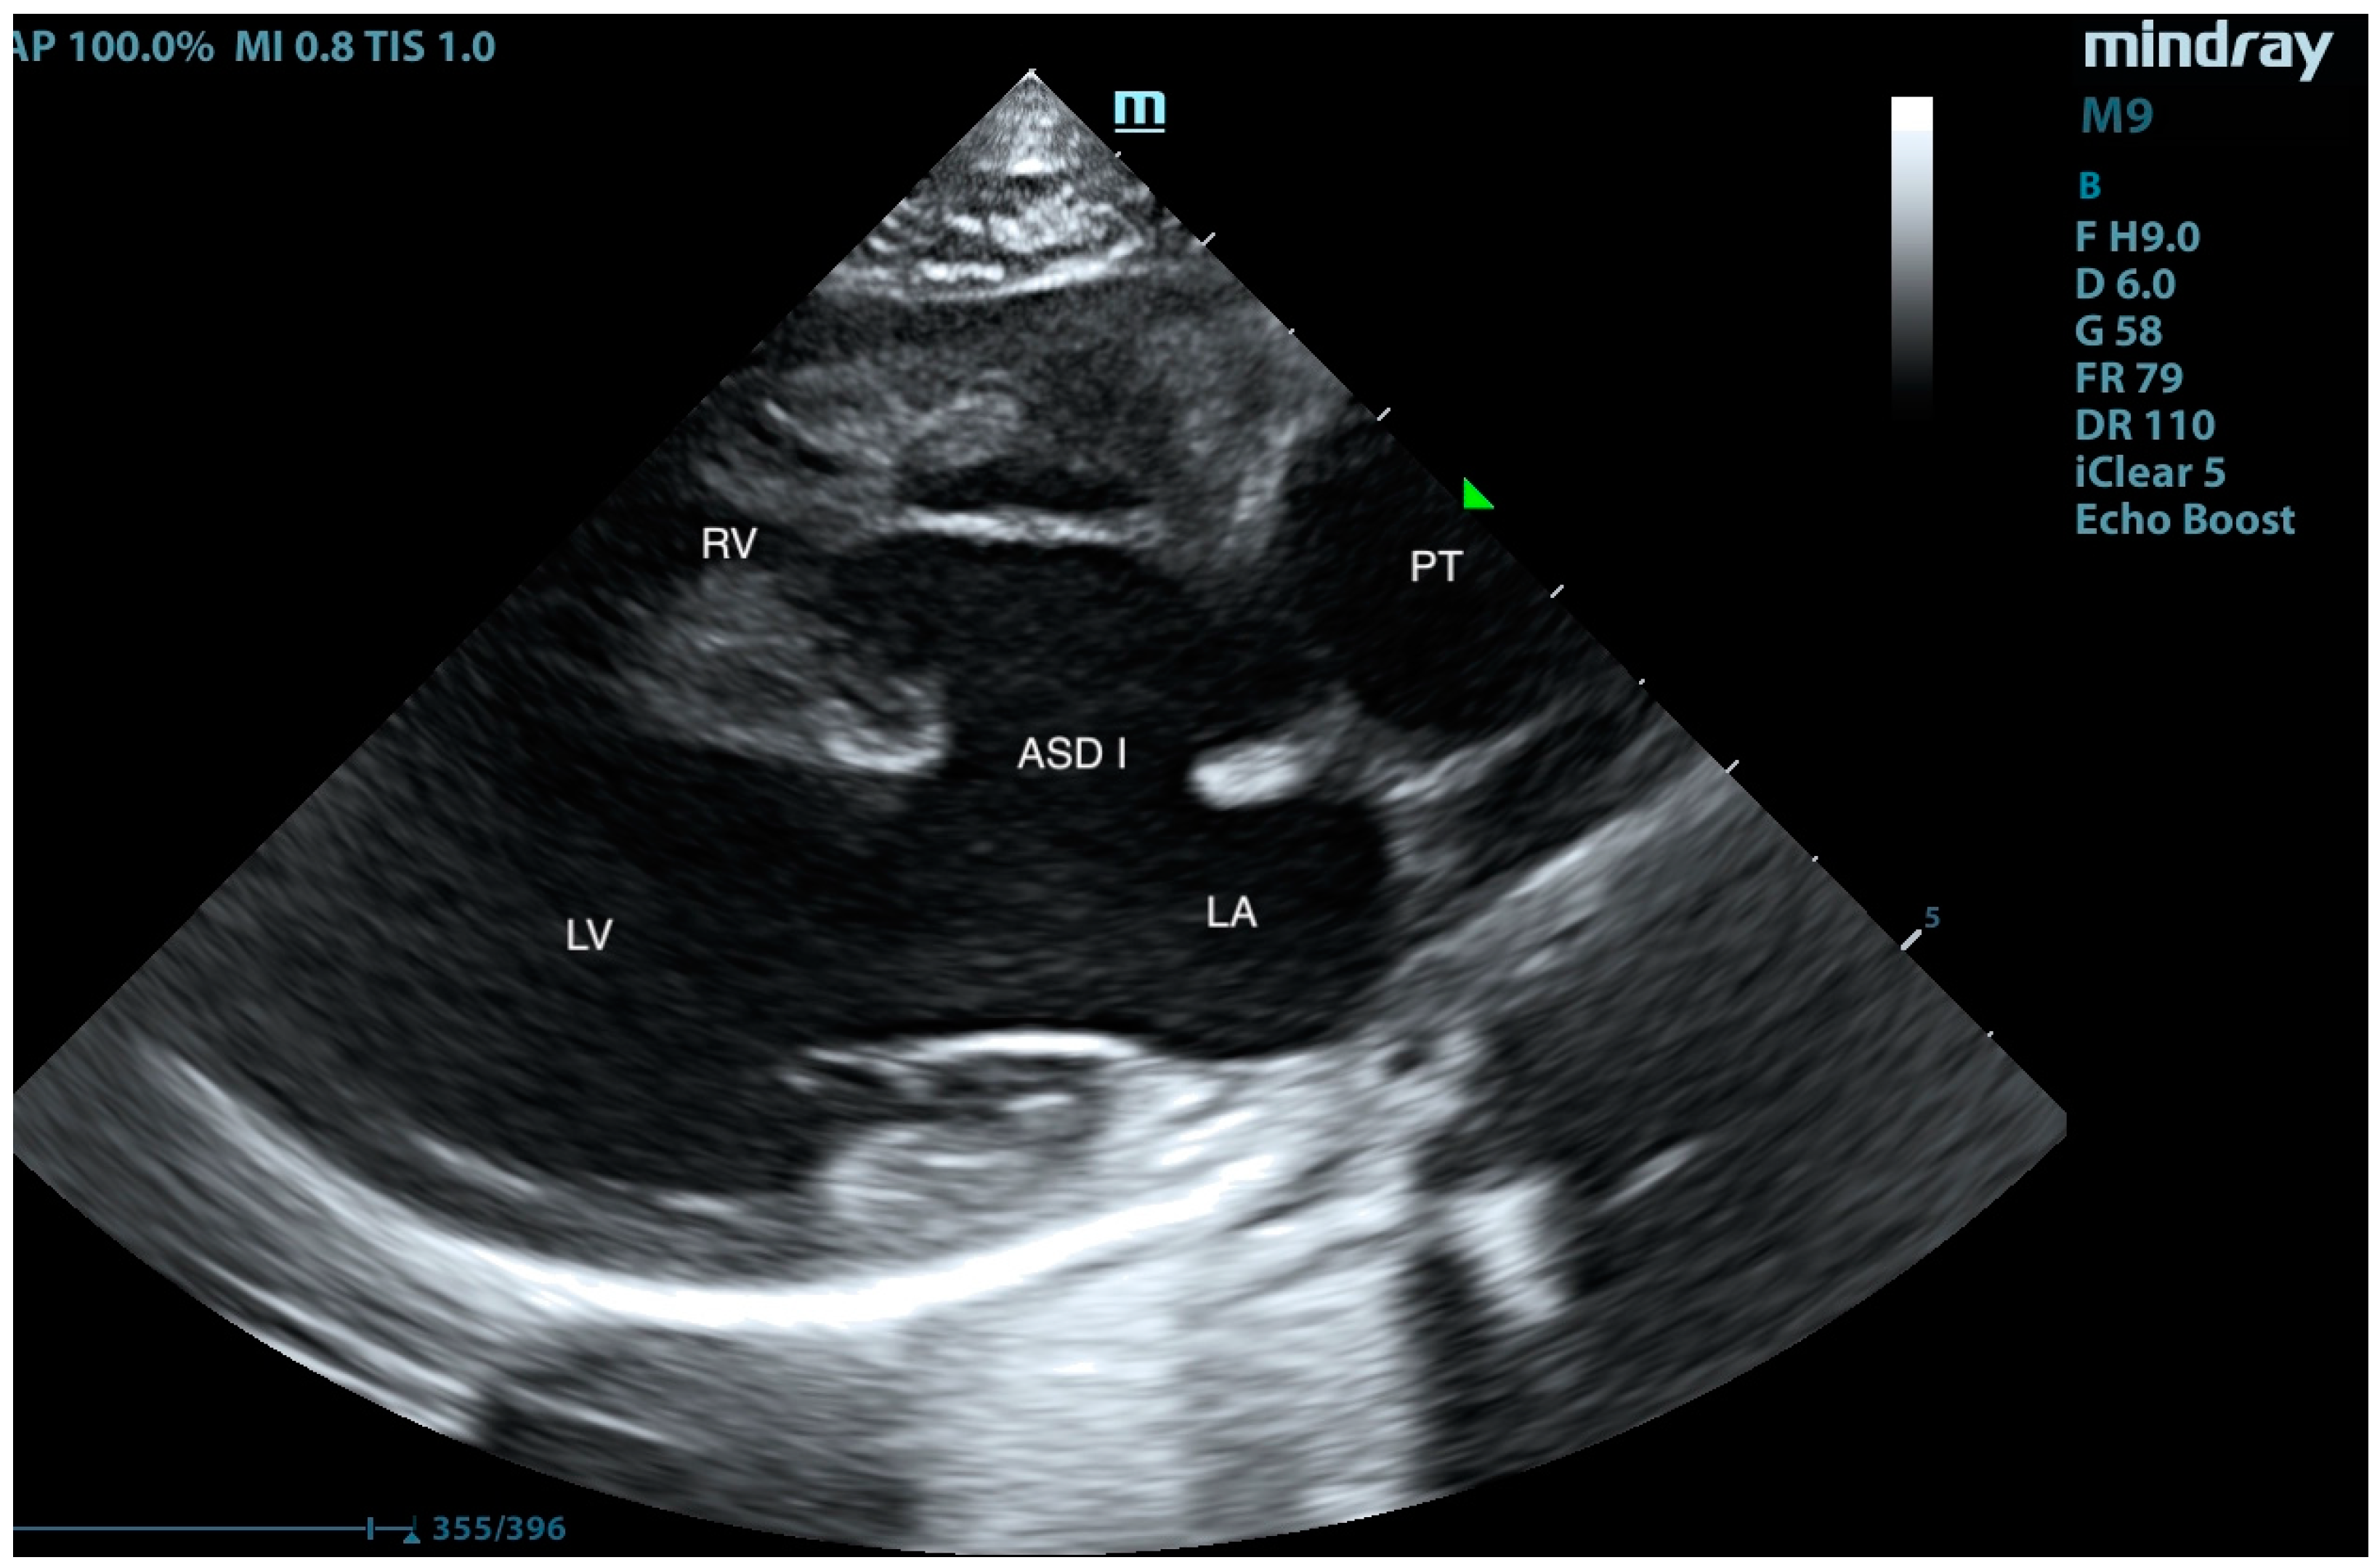

2. Case Presentation